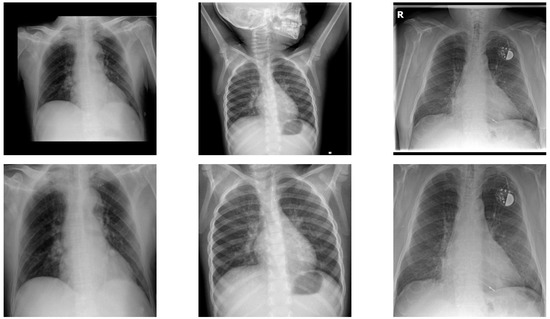

3.2.2. Lung Segmentation